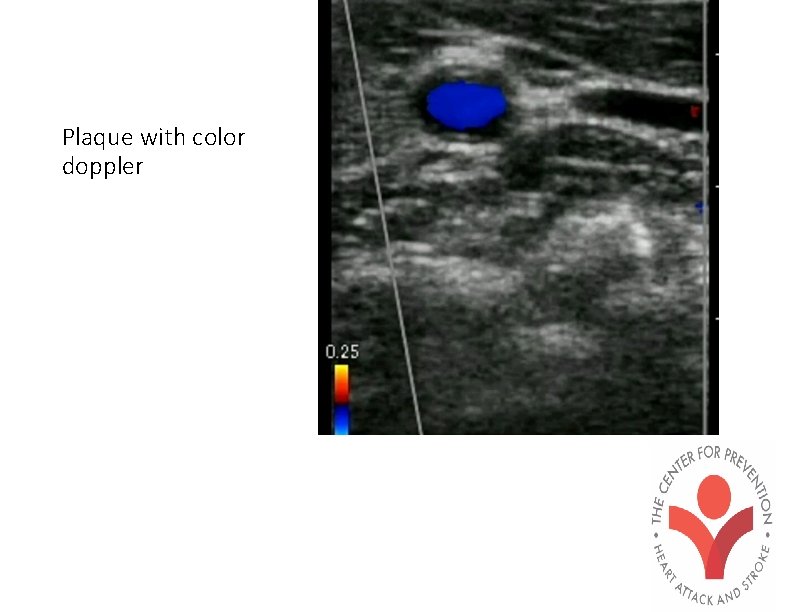

Plaque with color doppler